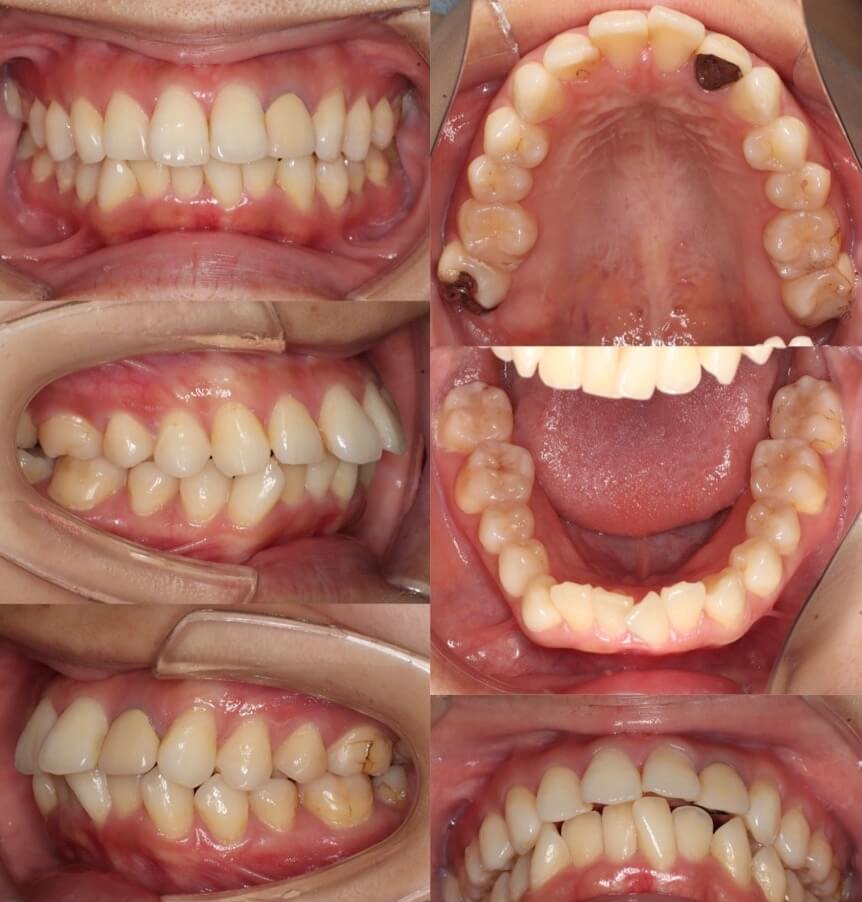

小学生女子・唇側矯正装置・前歯傾斜型

<顔のビフォーアフター>

<症例概要>

主訴:前歯の歯並びが悪い

年齢・性別:10歳女子(小学生)

住まい:千葉県八千代市

症状:上下顎前突・叢生

治療方針:抜歯空隙閉鎖(中等度固定)

治療装置:唇側矯正装置

固定装置:ナンスのホールディングアーチ

抜歯:上下第一小臼歯(計4本)

治療期間:1年11か月

リテーナー:上プレートタイプ+下フィックスタイプ

治療費用:968,000(税込)

代表的副作用:痛み・治療後の後戻り・歯根吸収・歯髄壊死・歯肉退縮

▶︎その他の副作用

前から2番目の歯がクロスしている叢生症例です。前歯の噛み合わせが悪い事とやや口が閉じにくそうであったため、上下左右の合わせて4本の小臼歯を抜歯し矯正治療を行いました。歯並びにでこぼこが少ない方に抜歯矯正治療を提案すると、最初はお子様や保護者様に強い拒否感がある事もあります。しかし、最終的にはゴールを考えると、最終的には皆さん納得してくれます。仕上がりを見ても分かると思いますが、前歯がしっかり噛んでいます。歯を4本減らしても噛む面積は前より増えているわけです。